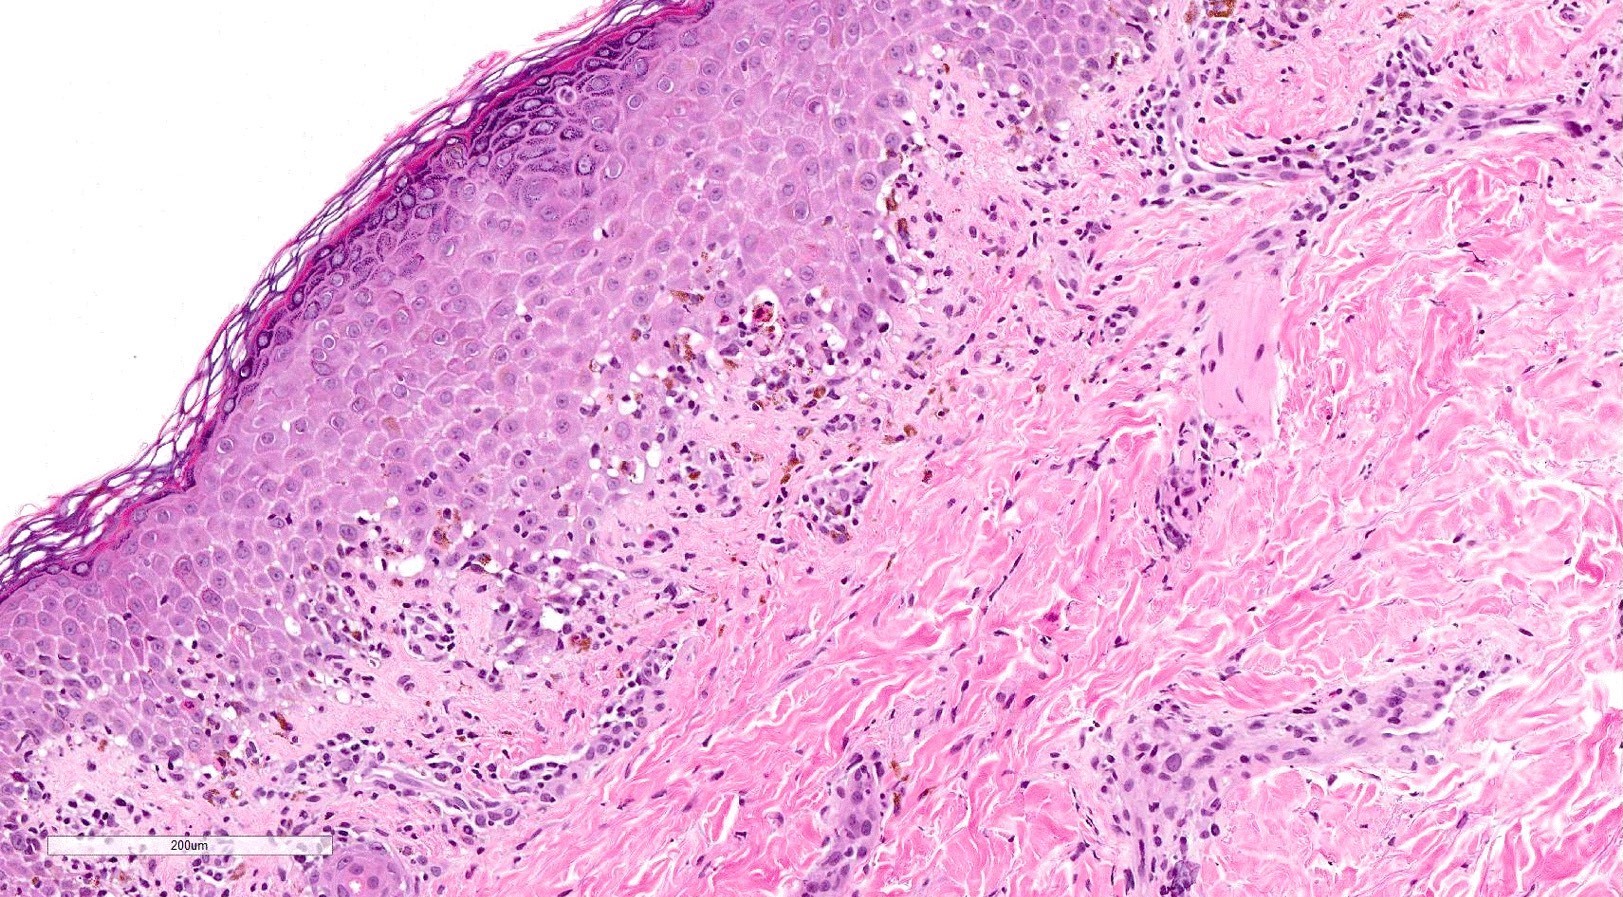

Microscopic (histologic) description

- Acute GVHD (Patterson: Weedon's Skin Pathology, 4th Edition, 2015)

- Mild to moderate superficial perivascular lymphocytic infiltrate with exocytosis of inflammatory cells into the epidermis and basal vacuolation, interface dermatitis

- Scattered, shrunken, eosinophilic keratinocytes with pyknotic nuclei, at all levels of the epidermis; often accompanied by 2 or more lymphocytes, producing the satellite cell necrosis - lymphocyte associated apoptosis

- Occasionally, rare eosinophils can be present; melanin incontinence is prominent in patients with darker skin types

- If severe, subepidermal microvesicles, subepidermal blisters and epidermal necrosis

- Lymphocytic infiltrate in GVHD after solid organ transplantation is usually brisk in comparison to the sparser inflammation following bone marrow transplantation

Microscopic (histologic) images

Contributed by Silvija P. Gottesman, M.D. and Ohoud Aljarbou, M.D.